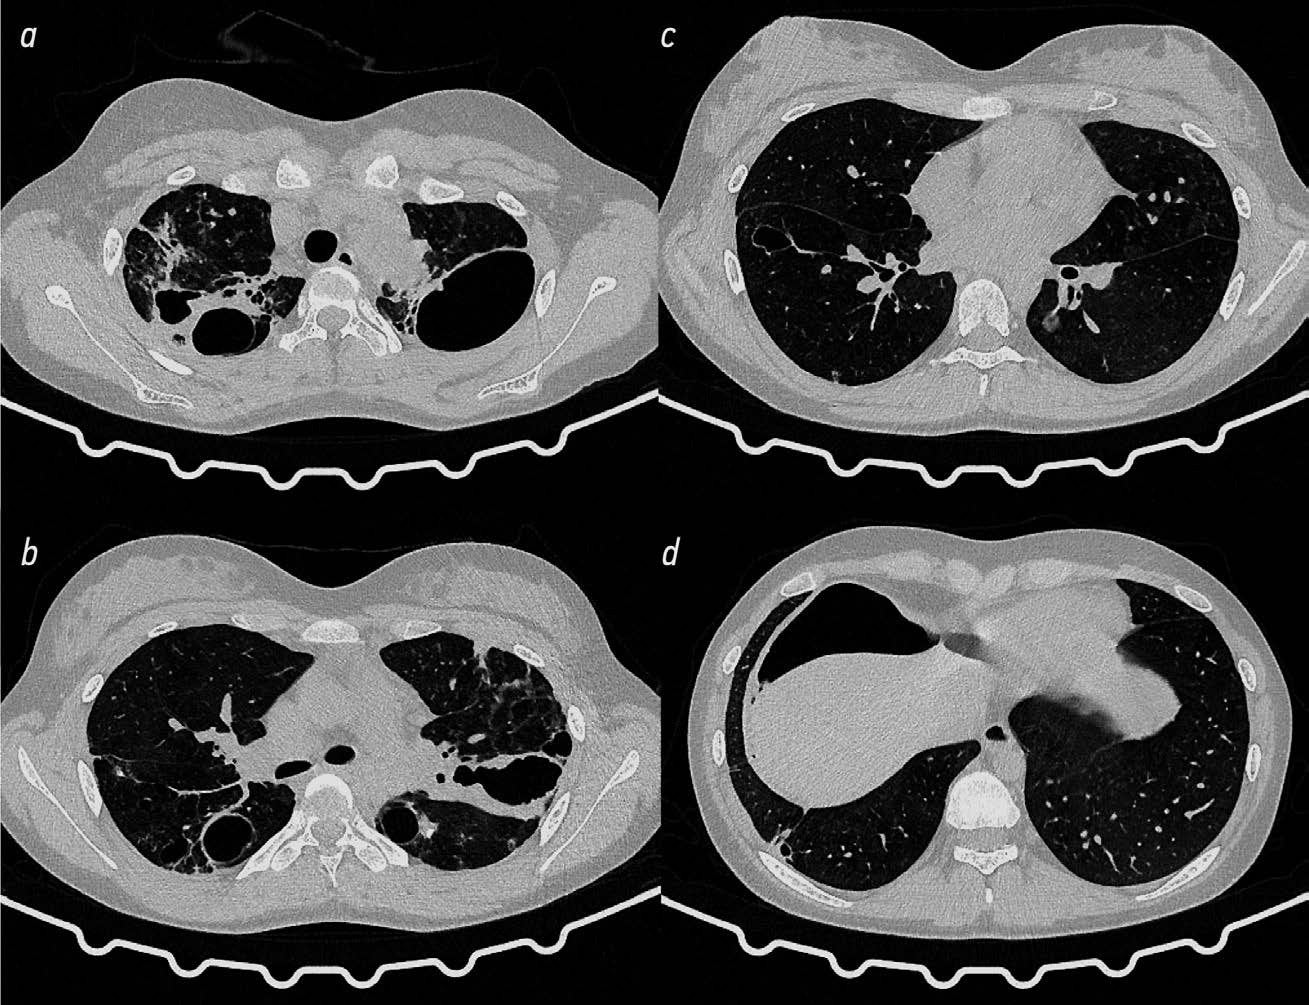

На КТ ОГК через 6 мес. (рис. 2) верхние доли и SVI обоих лёгких уменьшены в объёме. В верхней доле правого лёгкого определяются множественные разнокалиберные воздушные полости и участки пневмосклероза с мелкими бронхоэктазами. Аналогичные изменения имеются в апикальной части SVI, где размеры наиболее крупной полости составляют 44×46×46 мм. В SVIII субплеврально определяется тонкостенная полость 18×17×20 мм с мелкими кальцинатами в стенке. Пневматизация лёгочной ткани неравномерная за счёт участков панлобулярной эмфиземы. Во всех сегментах сохраняются рассеянные плотные очаги. Положительная динамика по сравнению с КТ ОГК при поступлении в виде закрытия одной из полостей в SVI левого лёгкого.

Рис. 2. Компьютерная томография органов грудной клетки через 6 мес. после клапанной бронхоблокации: положительная динамика в виде закрытия одной из полостей в SVI левого лёгкого (описание в тексте).

Fig. 2. Computed tomography of the chest organs 6 months after valvular bronchoblocation: positive dynamics when one of the cavities in SVI of the left lung was closed (description in the text).